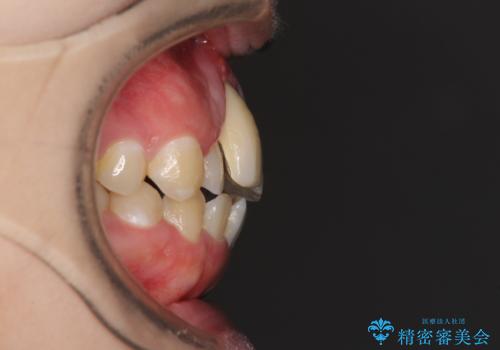

- 中学生の頃にぶつけた前歯に不格好なクラウンが装着されており、出っ歯な印象になっていることを気にして来院された患者様です。

ぶつけてしまった歯は保存が困難な状況であったので抜歯をし、ワイヤー矯正により歯列を整えつつ前歯の突出感を解消することとしました。

前歯の補綴治療はインプラントかブリッジかで悩んでいました。

周りの歯にむし歯がないため、インプラントがお勧めとなりますが、事故による骨欠損が大きく、歯肉ラインを整えるのが困難という問題がありました。